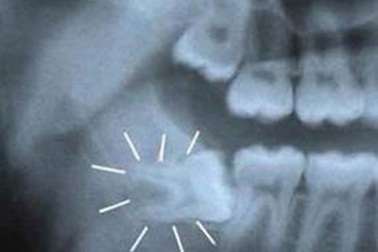

Đau khổ như mọc răng khônVào một ngày đẹp trời, chiếc răng khôn tự dưng chồi lên. Nhẹ thì gây nứt lợi, vết thương sưng tấy, mưng mủ, đau nhức cả hàm. Nặng hơn khi răng khôn mọc lệch, mọc ngầm sẽ dẫn đến đau tuỷ răng, viêm hạch góc hàm, gây rối loạn tiêu hoá và nhiều biến chứng khác.

Hàng loạt “rắc rối” vì răng khônQuá trình mọc “răng khôn” số 8 gây không ít rắc rối cho nhiều người bởi đây là răng mọc sau cùng, dễ gây mọc xiên, lệch, gây đau, thậm chí viêm nhiễm lan tỏa, nhiễm trùng huyết, có trường hợp tử vong. Thế nhưng nhiều người vẫn cam chịu không dám đi can thiệp, nhổ răng vì sợ ảnh hưởng dây thần kinh.

Loại bỏ 4 răng khôn mọc lệch cùng lúc an toànRăng khôn mọc lệch gây ra nhiều vấn đề phiền phức, khó chịu như: giắt thức ăn, gây sâu răng bên cạnh, sưng đau, viêm lợi trùm… Sự khó chịu này còn gấp 4 lần, khi anh N.H.M.Đ, 18 tuổi cùng lúc có 4 chiếc răng khôn mọc lệch.

Răng số 8 biến chứng có thể là vấn đề của … ung thưTheo thống kê của Tổ chức chăm sóc răng miệng Hoa Kỳ, 85% răng số 8 (răng khôn) phải nhổ bỏ thay vì được tồn tại suốt cuộc đời. Nếu không được xử lý kịp thời có thể dẫn đến những biến chứng tại chỗ nguy hiểm.